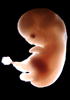

Carnegie Stage 20 (50 post-ovulatory days)

Most embryos at stage 20 are approximately 50-51 postovulatory days old and measure 21-23 mm in length. Distinguishing criteria for this stage include upper limbs slightly bent at the elbows, short stubby fingers, hands curving over the cardiac region but still far apart from each other, and a fringe-like vascular plexus that marks growth centers laterally in the superficial tissues of the head.

Although some of the photographs below show abnormal embryos, the animations and MRI slice images all depict normal embryos. Abnormal embryos are noted in the titles of the large photos when they are opened.